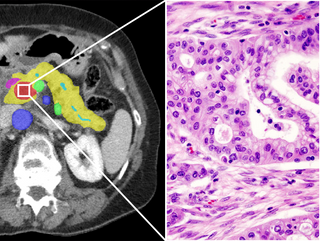

The Computational Pathology Group develops, validates and deploys novel medical image analysis methods based on deep learning technology.

Automated tumor detection